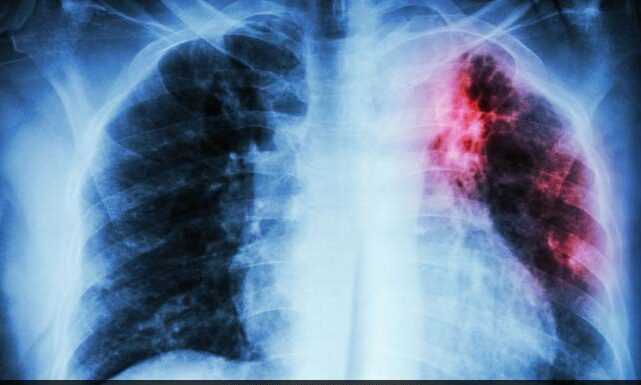

نیویارک (ہیلتھ ڈیسک): طبی سائنس میں جدید ترین پیشرفت کے باوجود ٹی بی اب تک خوفناک مرض کی صورت میں موجود ہے اور بالخصوص غریب ممالک میں جانوں کا خراج لے رہا ہے۔ تاہم اب نو دریافت مرکب سے اس کے مؤثرعلاج کی امید پیدا ہوئی ہے۔اس ضمن میں بل اور میلنڈا گیٹس فاؤنڈیشن نے تحقیقات اور مطالعات کیے گئے ہیں جو فروری 2023 میں اختتام پذیر ہوئے ہیں۔ کورنیل یونیورسٹی کے ماہرین نے اس مرکب کو تیار کیا ہے جس کا نام سی ایل بی 073 رکھا گیا ہے۔ یہ مرکب ٹی بی کی وجہ بننے والے ’مائیکوبیکٹیریئم ٹیوبرکلوسس‘ کو تیزی سے مفلوج کرکے اسے تباہ کر دیتا ہے۔

کورنیل یونیورسٹی میں واقع کالج آف ویٹرنری میڈیسن (سی وی ایم) کے پروفیسر ڈیوڈ رسل اور ولیم کاپلان نے یہ تحقیق کی ہے۔ توقع ہے کہ بہت جلد انسانوں پر آزمائش شروع کی جائے گی۔ ماہرین نے کئی تجربات کے بعد غور کیا ہے کہ سی ایل بی 073 بیکٹیریا کے کاربن کا راستہ روکتا ہے۔ اس طرح ٹی بی کا بیکٹیریئم مرنے لگتا ہے۔

ماہرین نے اس مرکب کو چوہوں پر بھی آزمایا ہے جس کے بعد ٹی بی کی ادویہ کی تاثیر میں اضافہ دیکھا گیا۔ ان میں این آئی ایکس ٹی بی کا مروجہ طریقہ علاج ہے جس میں تین ادویہ ملاکر دی جاتی ہیں۔ توقع ہے کہ اس سے ٹی بی کے خلاف ادویہ کی طاقت بڑھانے یا ان کی تاثیر بڑھانے میں بھی مدد مل سکے گی۔